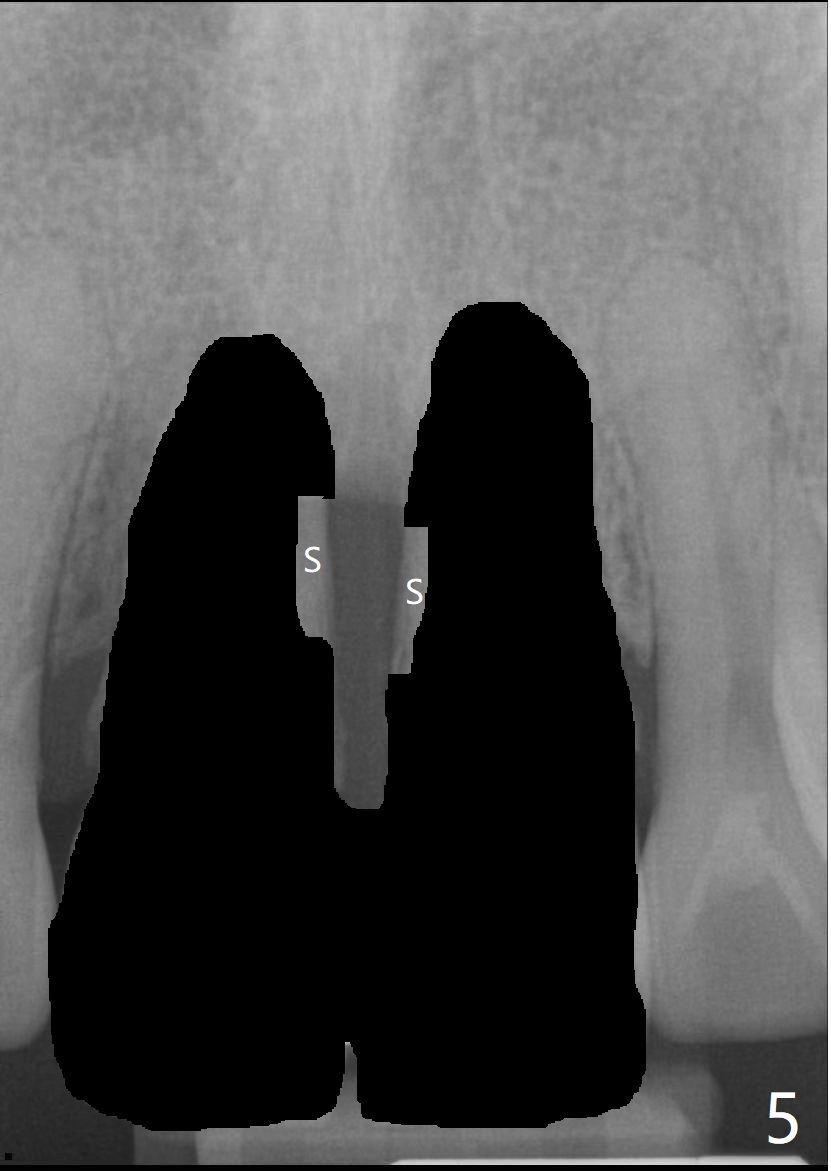

40几岁,身体无其它疾病(图一),全面检查,包括CT,取模做suck down stent/临时牙冠。第一种方法,保留一个牙根(图二:例如8号牙),减少两个牙齿之间软硬组织萎缩,一个植牙(绿色,至鼻底),基台(粉红色),临时悬臂桥,植体周围以及龈乳头下植骨(红圆圈)。图三显示两个牙齿都拔除,P:龈乳头,缺骨。为了在龈乳头下面植骨,分离它的根部,往冠方推移(图四:箭头),在产生的空间里放置骨粉(红圆圈)。也可以在颊侧近中保留部分牙根(socket shield,图五:S),然后游离龈乳头根部,推移,植骨(图六),最后植入两个植体。